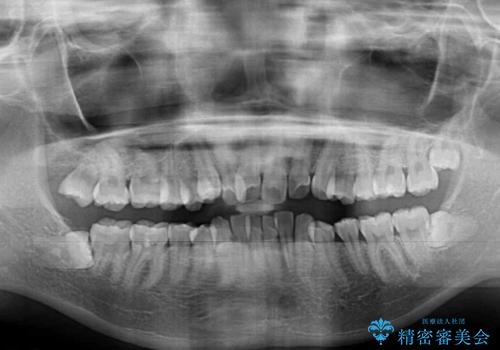

- 出っ歯とデコボコを気にして来院された患者様です。

口元の突出感を改善するため、上下左右第一小臼歯4本の抜歯を行い、ワイヤー装置による矯正治療を行うこととしました。

治療前の上下正中はずれていましたが、骨格的な上下左右差はあまり認められなかったため、正中を揃えて治療を終えることができました。